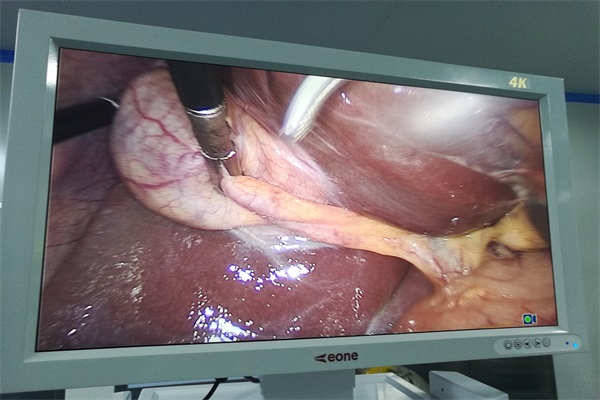

臨床中,經小切口剝離出腔隙,插入內窺鏡鏡頭和各種器械,完成一系列的操作,例如:切開、剝離、電凝、沖洗、縫合等都在肉眼監(jiān)測顯示器屏幕下進行操作,代替了傳統(tǒng)。

雖然內窺鏡技術仍有不完善的地方,但它有著傳統(tǒng)方式無法比擬的優(yōu)越性。電子內窺鏡的成像原理是什么?電子內窺鏡的成像方法利用安裝在電視信息的光源發(fā)出的光,將光導入經內窺鏡導光纖維檢查的體內,CCD圖像傳感器接收從體內粘膜面反射的光,將其轉換為電的信號,將該信號傳輸到電視信息中的電線,然后通過電視信息存儲和處理該電的信號,傳輸到電視顯示器,顯示被檢查器的官的彩色粘膜圖像。內窺鏡設備技術怎么樣?對于這醫(yī)用設備上還有哪些疑問可直接與客服聯系。